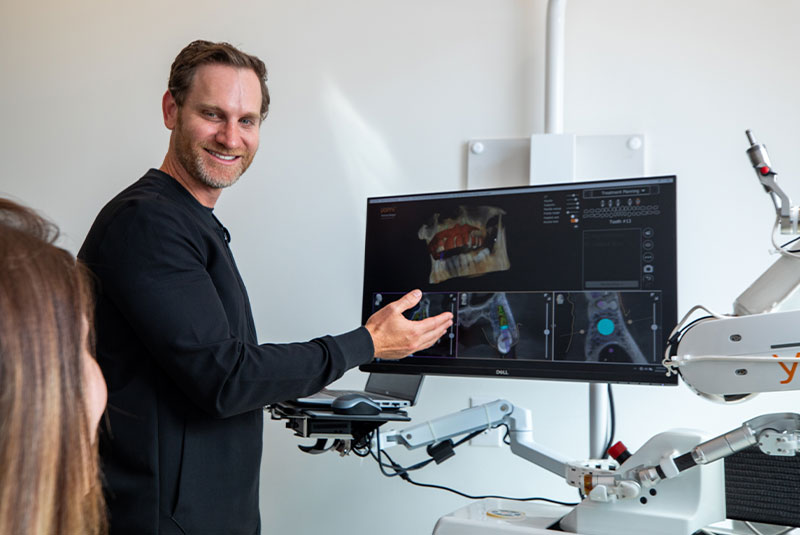

Our implant dentist Dr. Aaron Cohenour has placed more than 1,500 dental implants, is certified in IV sedation, and has a successful track record placing full mouth dental implants. When you choose Restoration Dental for dental implants in Edmond, OK, you’ll achieve better oral health and an improved quality of life that comes with a restored smile!

Restoration Dental stands out as the premier choice for dental implant placement due to our extensive experience and track record of success.

With more than 1500 dental implants placed, Dr. Aaron and our skilled team of experts have the expertise and precision necessary to deliver exceptional results. We prioritize patient satisfaction and utilize the latest techniques and technology to ensure optimal implant placement and long-term success.